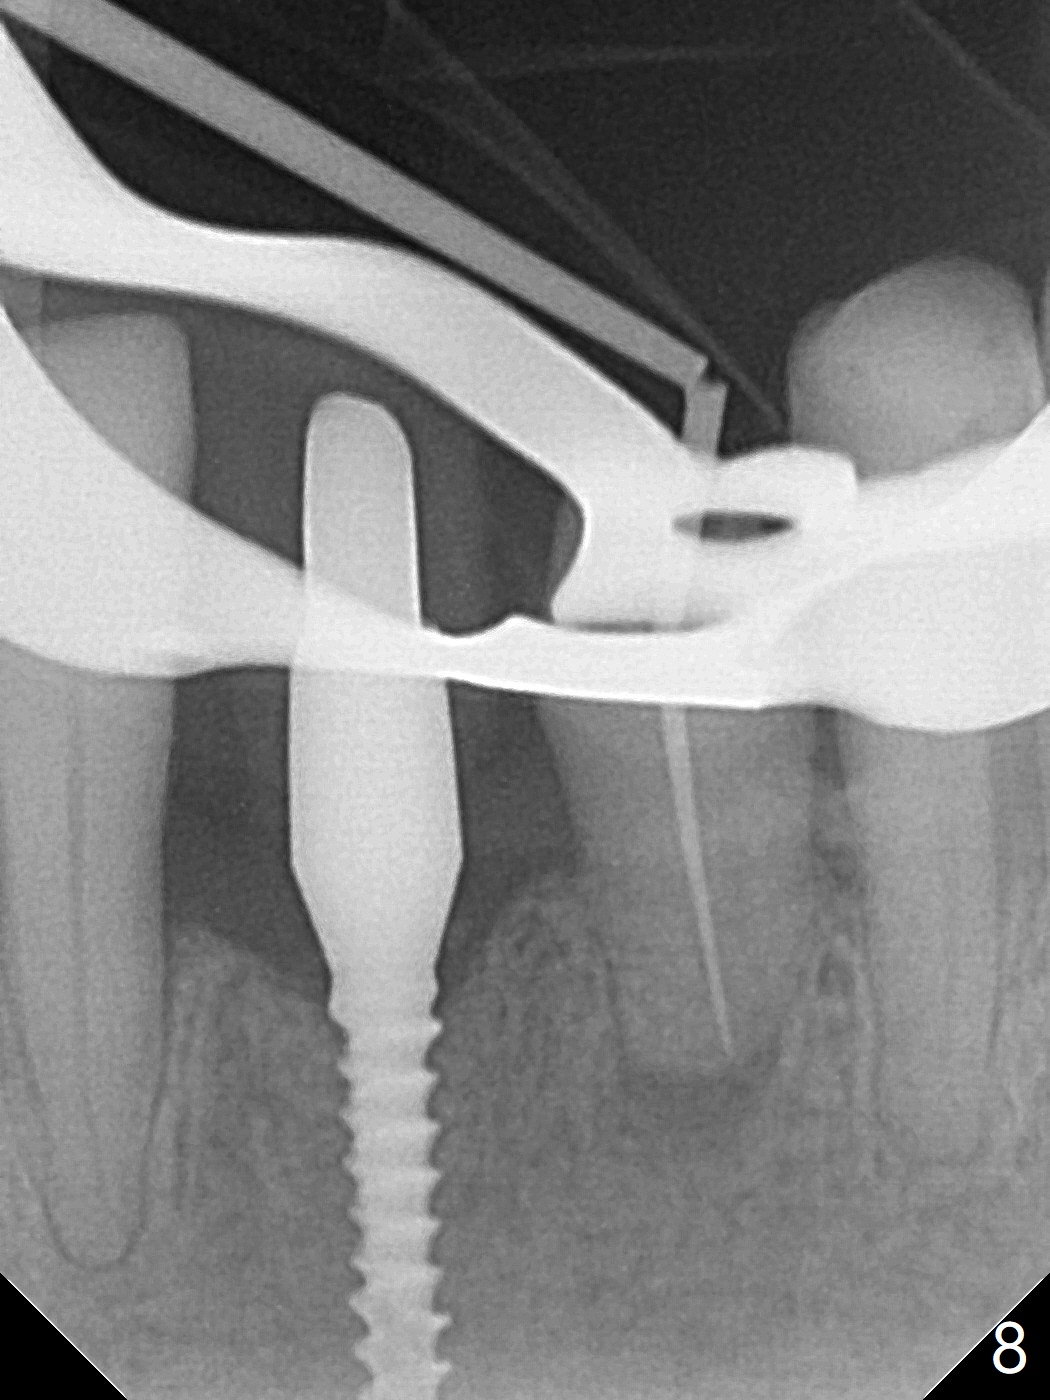

左下第一磨牙(#19)牙槽嵴狭窄,2.2毫米钻头完成导板钻洞后,舌侧骨板开始破裂(图一:<),打消牙槽嵴劈开术念头,放置2.5x8.5毫米一段式植体(图二(8.5毫米是最短植体)),好像离下齿槽神经管还有一定距离,适当植入深些(图四:箭头,15Ncm)。右下中切牙缺牙区牙槽嵴也十分狭窄(图四),最后不得不徒手植入2x8.5毫米植体(图五,六,25Ncm)。如果按设计植入2x12毫米植体,颊侧,或者舌侧骨板更容易穿孔。术后3.5月牙槽嵴下降(图七:箭头),可能术中那里压力太大,今后牙槽嵴钻洞要大。24号牙根尖阴影(图七),完成根管治疗(图八)。19牙位牙槽嵴吸收也严重(图九)。其实术后4个月19牙位牙槽嵴吸收并不严重(图十一)。